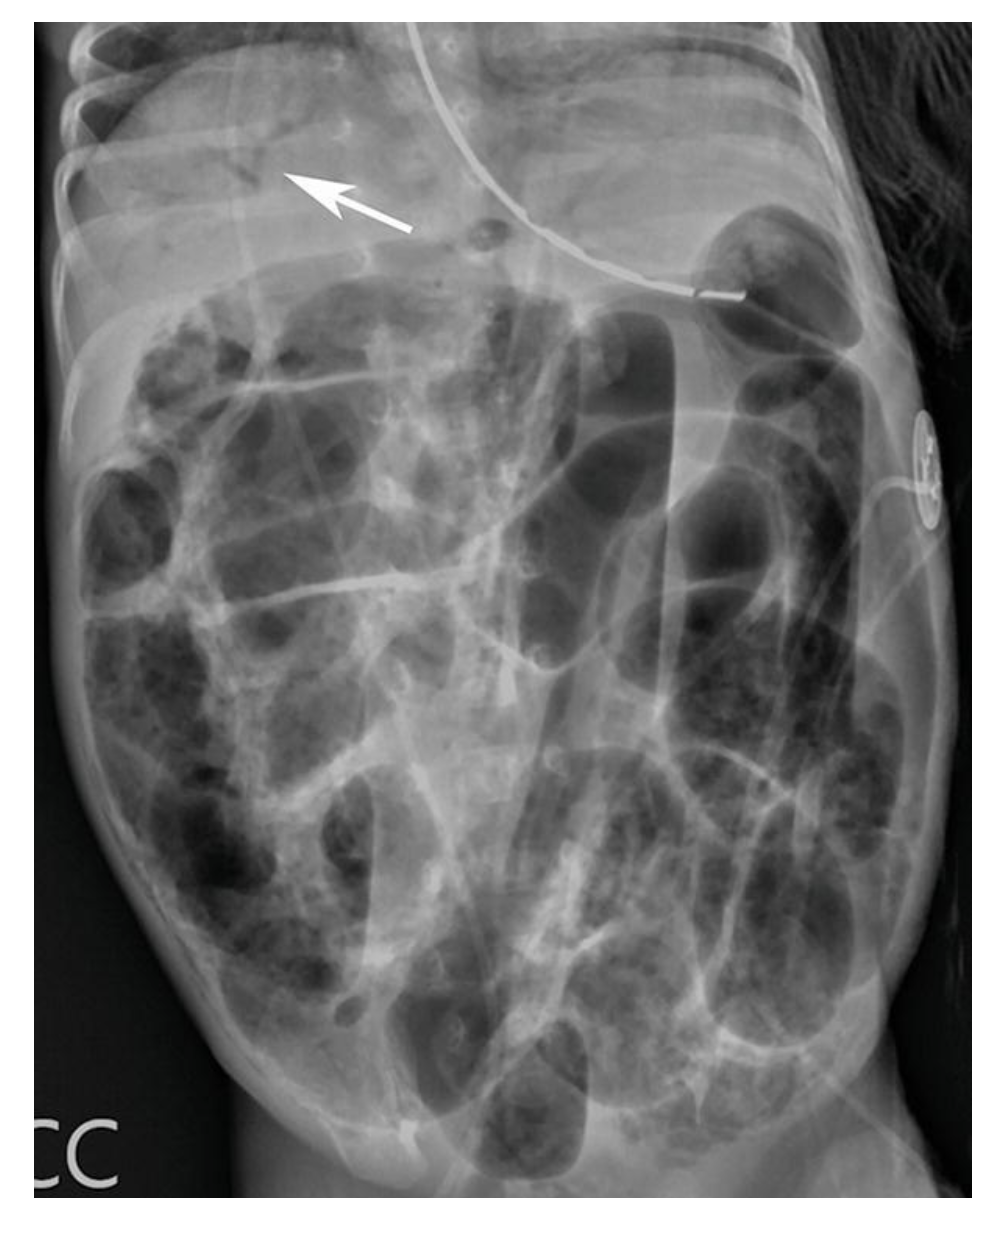

NEC with portal venous gas